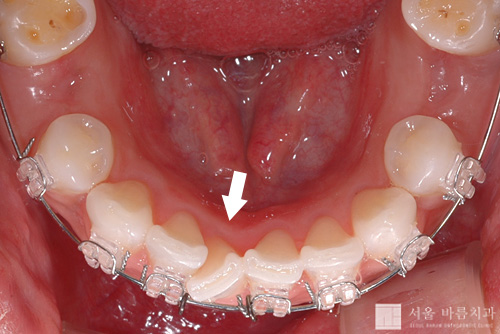

지난 달에 하악에 장치를 부착했습니다. 그러나 하악우측중절치(#41)가 많이 삐뚤어져 있어서 장치를 붙일 수 없었습니다(위의 사진에서 화살표가 가리키는 치아). 당분간 이 차아에 장치를 붙이기 위해서 주변에 공간을 만드는 작업에 주력해야 할 것입니다. 치아가 잘 움직이는 분들은 이 작업이 한달만에 쉽게 끝나지만, 그렇지 않은 분들은 여기서 은근히 시간이 많이 소비됩니다.